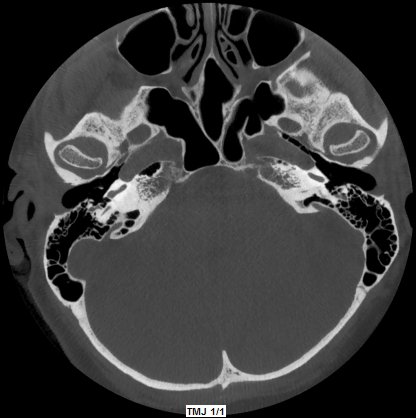

ATM Bocca Aperta